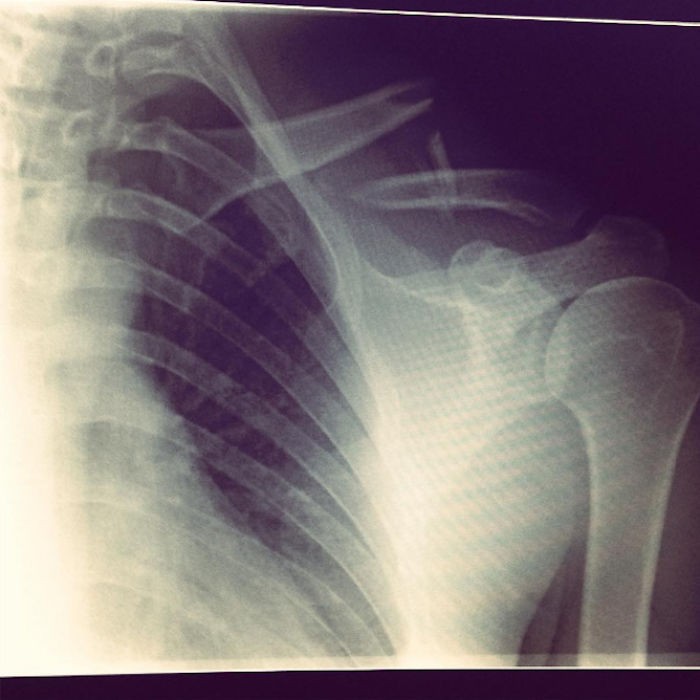

It was my first ski of the season in 2015, so I decided to celebrate by doing a flip. Shortly after, I was admitted to hospital with a broken collarbone and four fractured ribs. Not my finest work.

Three days later I was discharged, with a scar and some x-rays. The metal plate would hold my collarbone together while it healed, for the next year. Hospitals usually throw away the metalwork from surgeries like this, but I asked the surgeon to keep mine so that I could turn it into something. Scroll down to see the results!

Three days later I was discharged, with a scar and some x-rays that looked like this. The metal plate would hold my collarbone together while it healed, for the next year. It also only went off once at airport security – well done Berlin.